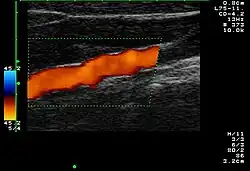

| Obrazy FMD w USG[30] | |

| Objaw „sznura pereł” w kolorowym doplerze u 51-letniej kobiety z zawężającą FMD wewnętrznej tętnicy szyjnej niskiego stopnia. |